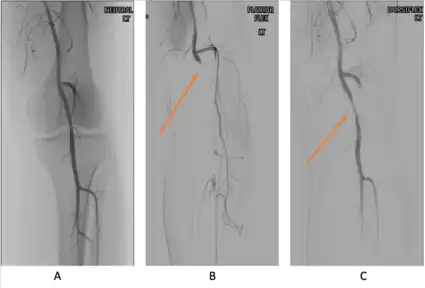

Angiograms of a patient diagnosed with popliteal artery entrapment syndrome of the left lower extremity. Image A shows a neutral popliteal artery before provocative maneuvers. Images B and C show the obstruction (orange arrows) enhanced with provocative maneuvers of plantar flexion and dorsiflexion, respectively.

PAES should be suspected in young healthy male patients with clinical symptoms consistent with compression of the vascular structures and without significant cardiovascular risk factors such as smoking.[13] Multiple imaging modalities are used to confirm the diagnosis of PAES.[23] Based on a systemic review by Sinha et al, digital subtraction angiography (DSA) is the most common imaging used for PAES diagnosis, followed by ankle–brachial index (18 percent), computed tomography angiography (CTA) (12 percent), magnetic resonance angiography (MRA) (12 percent), duplex ultrasonography (DU) (10 percent), exercise ankle-brachial index (4 percent), and other modalities (4 percent).[23] According to a recent study by Willimas et al, a combination of DU and MRA is far superior in diagnosing PAES.[24]

Provocative maneuvers can be used to improve visualization of PAES on the imagines.[25] The patient is initially positioned supine with the legs straight, and then instructed to forcefully plantar-flex. A plantarflexion force of 0 to 70 percent maximum has been shown to maximize the sensitivity and specificity for PAES diagnosis.[25] The DU can be a quick, inexpensive, and noninvasive initial screening for PAES. Flow velocities in the popliteal artery will increase, as the popliteal artery is compressed, which is reflected on the DU. If DU is negative but there is still strong suspicion for PAES, MRA or CTA with provocative maneuvers are needed as follow-up imaging. MRA would demonstrate a focal occlusion or narrowing of the mid-popliteal artery, post-stenotic dilatation, or aneurysm of the distal popliteal artery. If MRA or CTA is[13] non-conclusive, DSA may be used as a further option with a high sensitivity (> 97%) for PAES diagnosis.[23]